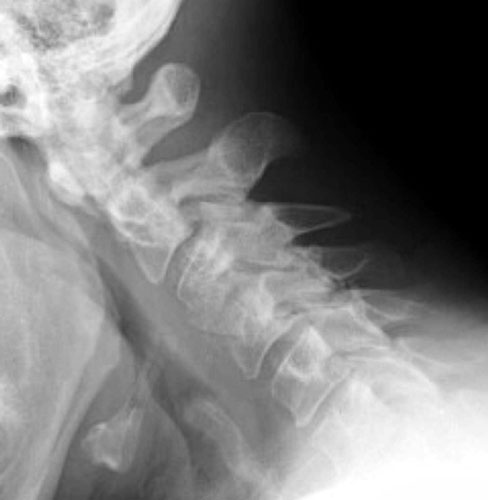

48 y.o. male with a history of alcohol abuse, depression and degenerative joint disease who is complaining of severe pain in his right neck and shoulder radiating down to his right third and fourth digit. The patient underwent anterior cervical disc fusion. Four months after the initial surgery, the patient still had pain but this time numbness was on flexion mainly and localized to the C5 region.

Lateral flexion and extension radiographs taken 6 months after surgery demonstrate incomplete graft incorporation (delayed healing). Furthermore, with flexion there is anterolisthesis of C4 on C5 (one level below the fusion) by 2-3 mm.